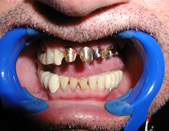

The term ‘Dental Implants’ refers to the surgical placement of artificial roots which help replace missing or badly damaged teeth. Other methods to replace missing teeth include dentures or bridges. The advantages of Implant tooth restoration is that it presents a more permanent solution.

Dentures are removable and tend to stay loose while they are worn. Full Dentures also affect the wearer’s diet. The ability to bite down can decrease by approx. 90%. Partial Dentures rely on adjacent teeth for help when biting. The long term effect of partial dentures leads to the loosening of the remaining teeth in the mouth. Dentures are recommended as a temporary resort or a last resort for patients that can not have implants due to medical complications, or lack of supporting bone.

Dental Bridges refers to the use of the adjacent teeth on either side of an empty space, to fill out the space and restore the function (or esthetics) of a missing tooth. Up until the invention of Implants, this procedure was considered the best way to restore the space created by a missing tooth. The two adjacent teeth are cut down and a cast metal and porcelain ‘suspension bridge’ is made to allow for the missing area to be filled out.

The advent of Dental Implants removed the need to cut down adjacent teeth to restore a missing tooth. In most cases an implant can fill out the missing space and restore the esthetic look of the area with no collateral damage. The adjacent teeth can live happily ever after, instead of needing to support a missing tooth, they now can enjoy the support of the adjacent implant crown.

The placement of Implants involves a short surgical procedure, which requires placing a screw-like structure into the jaw bone. The Bone and Implant need to integrate, this takes about 3-4 months, the Implant Fixture and final Implant Crown can be fitted.